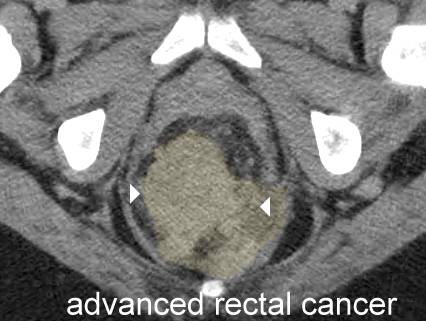

CT rectal cancer early,

CT rectal

cancer advanced,

CT rectal cancer advanced,

CT constricting T3 high rectal cancer